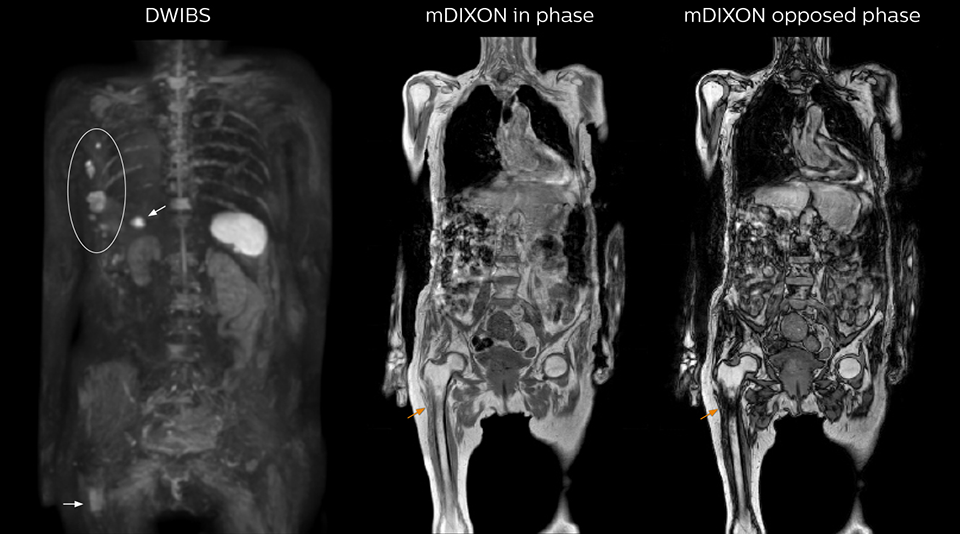

Radiologist Hiroshi Nobusawa, MD, PhD, explains that the coronal DWIBS protocol for whole body DWI is excellent for visualizing lesions in oncology patients. “About 90% of the DWIBS exams are done in this type of patients. The remainder of DWIBS exams are performed to gain information in cases of fevers of unknown origin,” he says. in image acquisition and postprocessing algorithms.”“mDIXON TSE sequences allow simultaneous characterization of morphological changes from the in-phase T2-weighted images and visualization of edematous changes, thanks to the water T2-weighted images from the same acquisition. Anatomical and morphological considerations could be a partial or complete ligament tear, a bony avulsion or hematoma.” “For soft tissue assessment mDIXON brings similar benefits. For example in one T2-weighted mDIXON TSE acquisition, having the multiple contrasts helps us assess abnormalities in peripheral nerves fascicles, which may be due to anatomical or inflammatory changes..” “In peripheral joints, we get good image quality in difficult areas with mDIXON TSE. Fat suppressed images appear homogeneous over the entire image, even with large coverage at 3.0T – for instance in scapular or hip girdles – or in the bearing areas or around metal prostheses*, where fat suppression is often deficient with STIR or spectral fat suppression, causing diagnostic difficulties. If a diagnostic image is right the first time, we don’t need to repeat or add a sequence.” “mDIXON TSE sequences allow simultaneous characterization of morphological changes from the in-phase T2-weighted images and visualization of edematous changes, thanks to the water T2-weighted images from the same acquisition. Anatomical and morphological considerations could be a partial or complete ligament tear, a bony avulsion or hematoma.” “For soft tissue assessment mDIXON brings similar benefits. For example in one T2-weighted mDIXON TSE acquisition, having the multiple contrasts helps us assess abnormalities in peripheral nerves fascicles, which may be due to anatomical or inflammatory changes..”

“mDIXON FFE allows us to quickly get information we need to assess the presence of fat. That gives us more information when we need to diagnose bone lesions, and when we are asked to judge fat-containing lesions such as hepatocellular or renal carcinoma,” Dr. Nobusawa says. “The mDIXON fat images can help us to differentiate fatty bone marrow from bone lesions. This is especially useful in elderly people, who tend to have fattier bone marrow. The water images provide a high signal-to-noise ratio in the intestinal canal, which is valuable for visualizing lesions in the colon,” he says.

Kawasaki Sawai Hospital’s whole body protocol also includes an mDIXON FFE sequence. Because mDIXON provides images for four contrast types – water only, fat only, in-phase and out-of-phase – from a single acquisition, it is useful in many ways.

“In-phase and out-phase sagittal T1-weighted FFE images help us to visualize and further characterize bone lesions such as metastasis and bone-marrow hyperplasia that have high signal on DWI. These images are also used throughout radiotherapy, to monitor changes in the fatty bone marrow.”